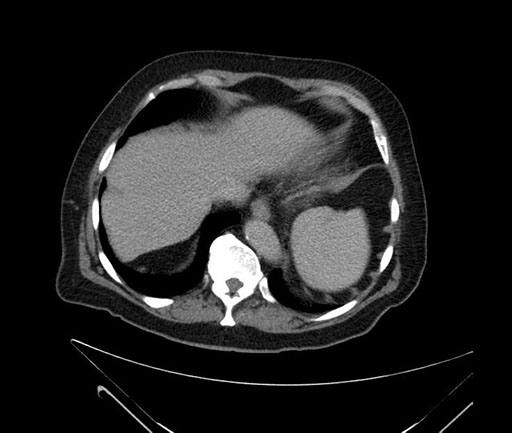

Axial - 3 months prior